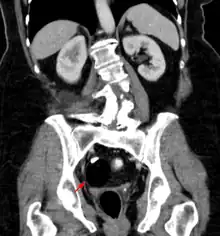

Les tératomes de l'ovaire

Les tératomes immatures de l’ovaire, souvent détectés à l'échographie, TDM ou IRM[21] sont potentiellement malins tout comme les tératomes testiculaires, qui sont généralement moins bien différenciés (donc avec un pronostic plus sombre). Des effets hormonaux, systémiques ou éloignés (ex. : encéphalite limbique paranéoplasique, encéphalite paranéoplasique anti-NMDAr)[22] sont possibles. Les métastases sont rares mais possibles (ex. : métastases neuroïdes matures d’un tératome ovarien[23]). Après ablation, des récidives sont possibles[24].